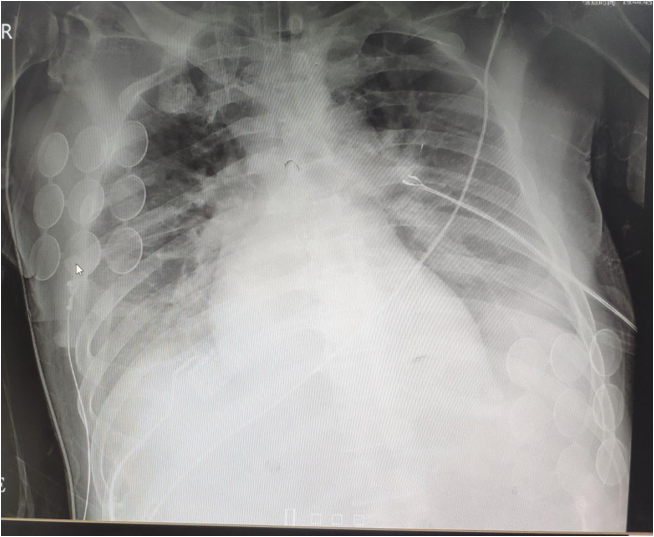

5.27及6.1查胸片示:双肺肺水肿,双侧大量胸腔积液,明显进展